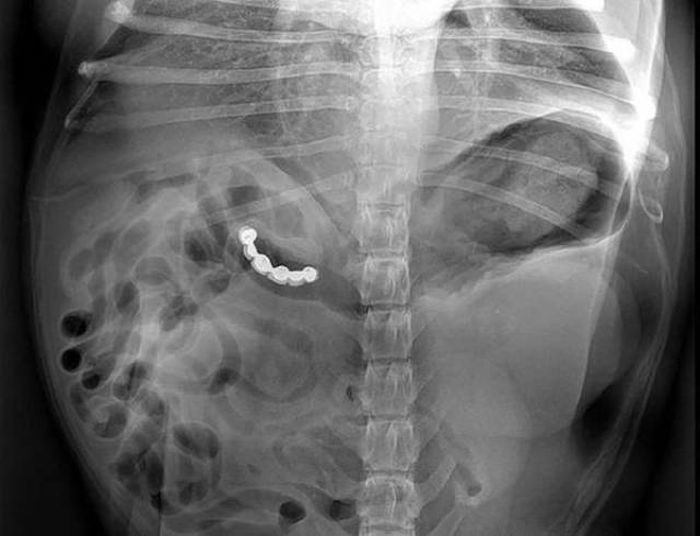

Предметы, которые не очень хочется видеть внутри себя

Под рентгеновскими лучами порой видны не только внутренние органы и кости, но и инородные тела, попавшие в организм

Истории попадания этих предметов в организм могут быть самыми невероятными и запутанными, но больше всего медиков интересует процесс их извлечения, впрочем, в этом заинтересованы и сами пациенты, допустившие нечто подобное со своим телом.